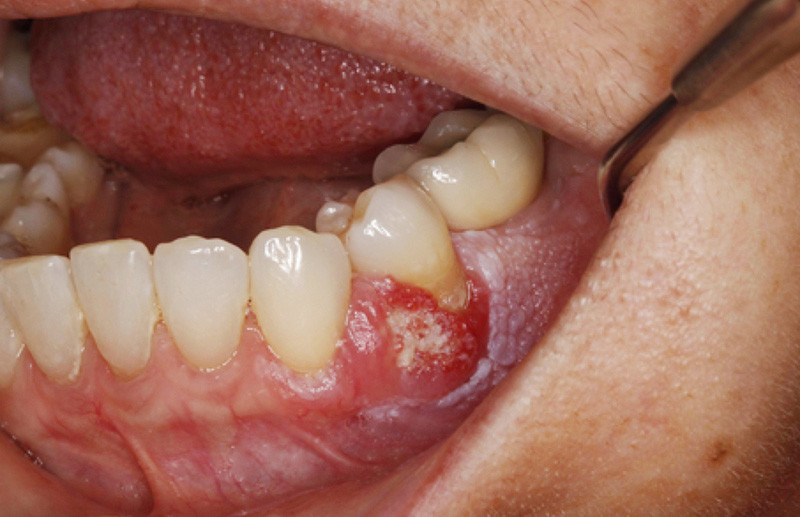

Examen clinique. On observait un remaniement de la fibromuqueuse gingivale vestibulaire et une tumeur gingivale vestibulaire intéressant principalement la papille interdentaire entre 33 et 34, avec une extension postérieure érythémateuse. Les limites de la lésion étaient assez nettes. Dans sa partie antérieure, il existait une zone papillomateuse blanchâtre où la pression faisait sourdre une substance blanchâtre, de consistance pâteuse. La gencive en dessous et en arrière de la lésion était recouverte par une kératose dont la surface avait un aspect framboisé.

L’examen histopathologique de la pièce d’exérèse a montré que la surface de la lésion était tantôt plane, tantôt papillaire, avec par endroits une épaisse couche de parakératose. L’épithélium comportait une alternance de zones atrophiques et de zones hyperplasiques. En profondeur, il existait un carcinome épidermoïde bien différencié dont certains lobules étaient centrés…